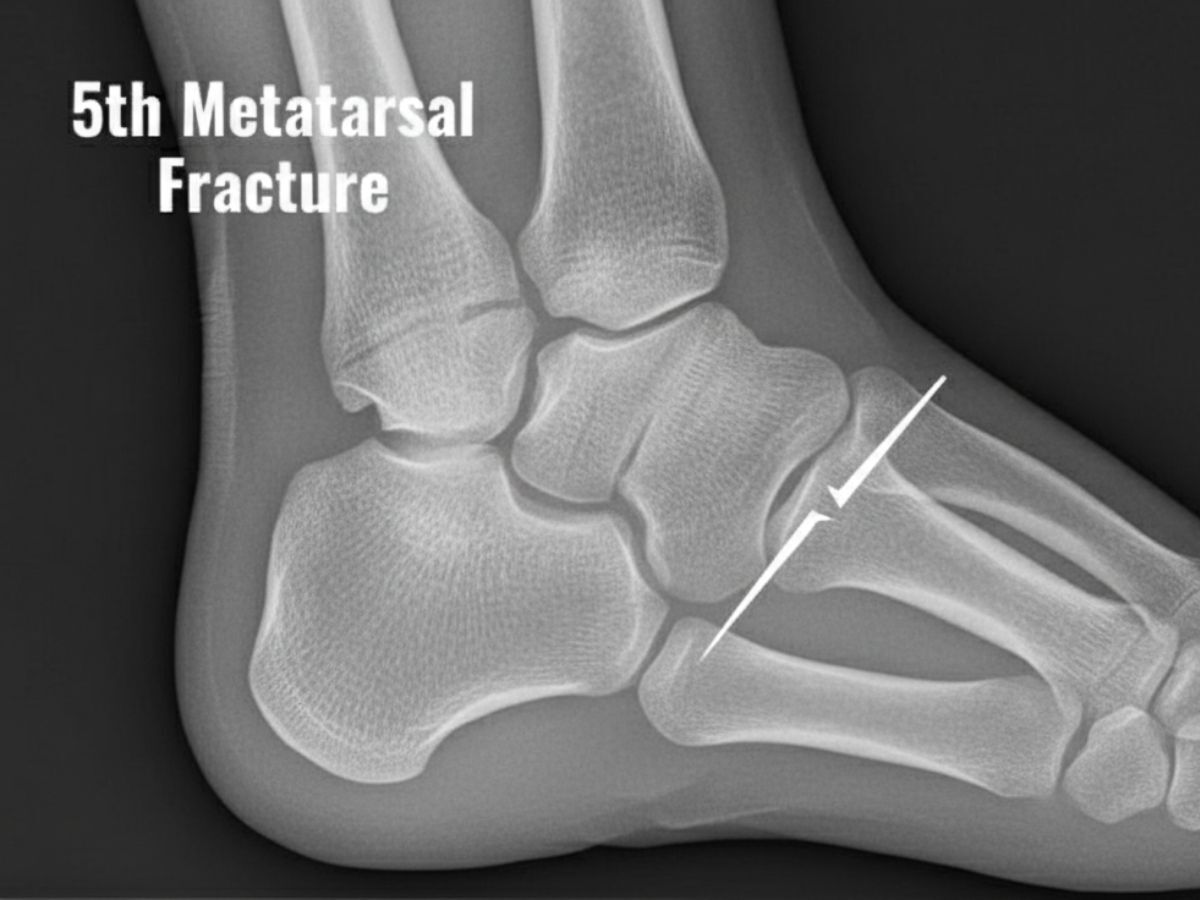

Understanding the 5th Metatarsal Fracture

The fifth metatarsal is one of the 5 lengthy bones within the foot, and its base is placed on the outer aspect of the foot. Fractures right here can be painful and debilitating, frequently attributable to acute injuries including twisting the foot or direct effects. Without proper remedy, those fractures can result in chronic pain, instability, and arthritis.

- How is a base of 5th metatarsal fracture diagnosed?

Diagnosis is made through bodily exam and imaging assessments which includes X-rays or MRI scans to decide the extent of the fracture.